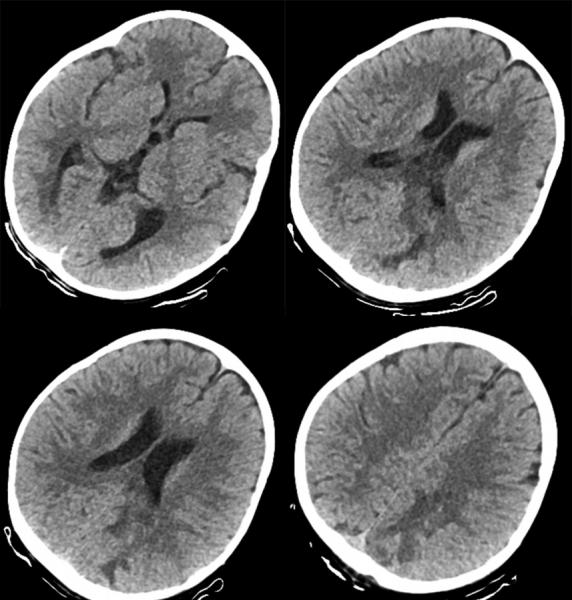

术后第一天复查见血肿清除